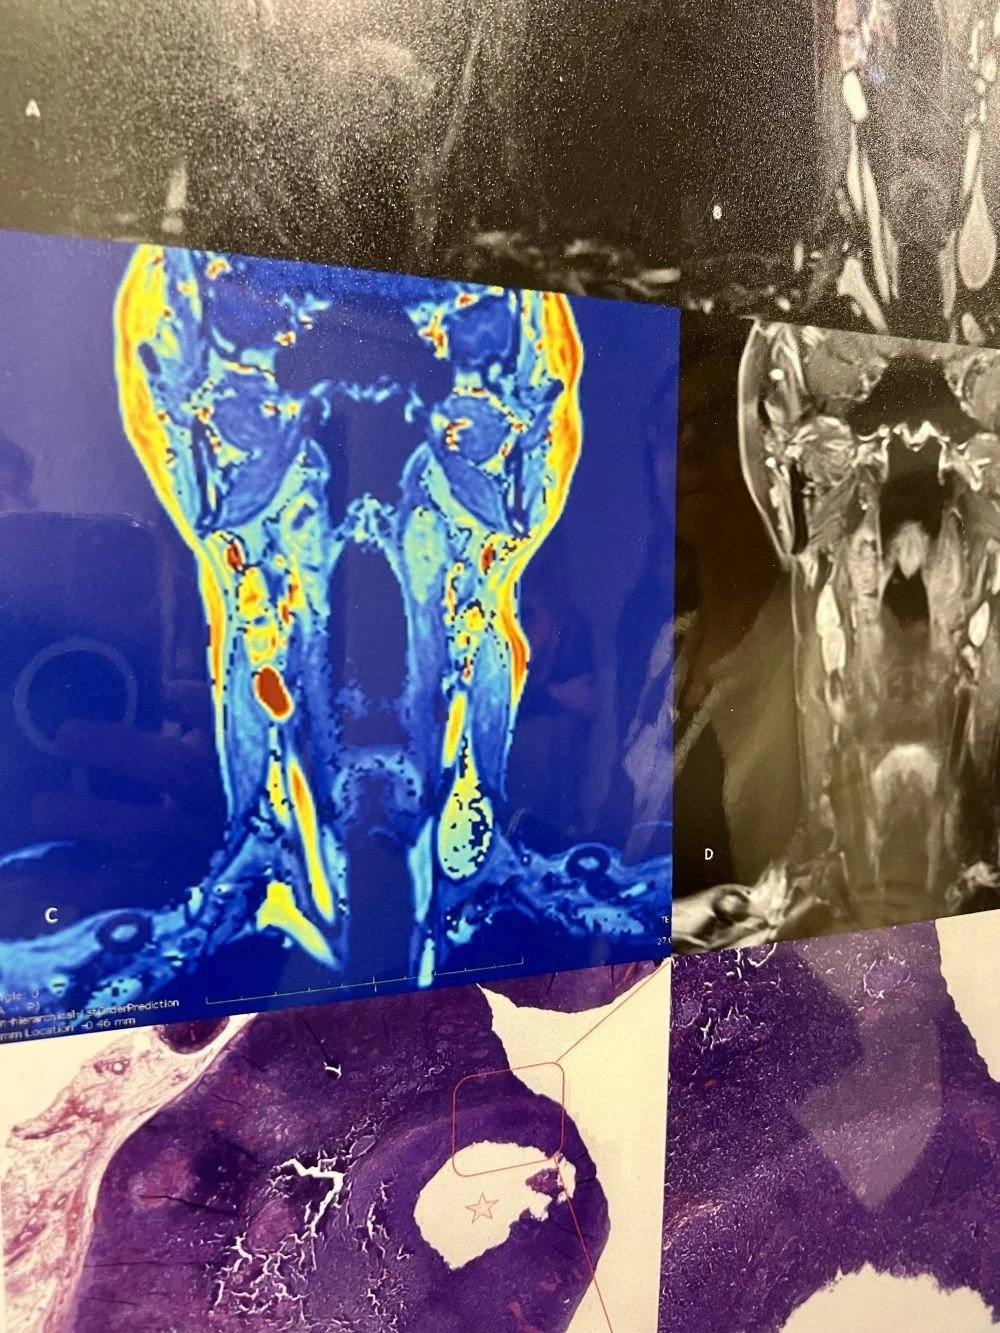

Προς το παρόν έχουμε χιλιάδες εικόνες υψηλής ευκρίνειας από το ανθρώπινο σώμα και αυτό είναι σημαντική εξέλιξη, επισημαίνουν οι επιστήμονες. Μάλιστα στο άμεσο μέλλον θα μπορούν να χειρουργούν με τη βοήθεια της «κινηματογραφικής ανατομίας» δηλαδή να παρακολουθούν με εξαιρετική λεπτομέρεια την περιοχή που επεμβαίνουν. Η τεχνολογία, ήδη μας βοηθά σε λιγότερο χρόνο να γίνονται περισσότερες εξετάσεις που δίνουν εικόνες εξαιρετικής ευκρίνειας από το ανθρώπινο σώμα, επισημαίνει ο Μ. May και εξηγεί πως η ΑΙ μπορεί να βοηθήσει - μέσω αλγορίθμου -τον ακτινολόγο να εντοπίσει έναν όγκο, και προσθέτει : «Τώρα βιώνουμε μια συναρπαστική εποχή, καθώς χτίζουμε υψηλής ανάλυσης δεδομένα, είμαστε η γενιά που αποθηκεύει αυτά τα δεδομένα. Δημιουργούμε αρχεία. Όμως, οι αλγόριθμοι θα πρέπει να τα επεξεργαστούν ώστε η επόμενη γενιά γιατρών να ωφεληθεί από αυτά τα προγράμματα που σήμερα ονομάζουμε ΑΙ».

Στον τομέα της διαγνωστικής και θεραπευτικής απεικόνισης, για παράδειγμα υπάρχουν πλέον εξελιγμένα μηχανήματα, όπως πρωτοποριακό σύστημα μαστογραφίας με καινοτόμα τεχνολογία απεικόνισης, αξονικός τομογράφος τεχνολογίας καταμέτρησης φωτονίων, PET/CT επόμενης γενεάς, μαγνητικός τομογράφος με δυνατότητα προσαρμογής στα ιδιαίτερα γνωρίσματα κάθε ασθενή, και προηγμένα απεικονιστικά μηχανήματα για την καθοδήγηση χειρουργικών επεμβάσεων.